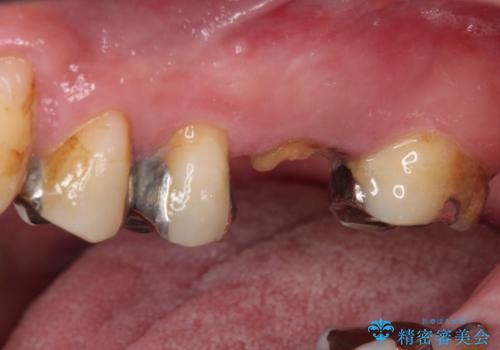

上顎の歯根のみとなった歯は抜歯が必要であったので、抜歯を行い、インプラントあるいはブリッジのよる補綴治療を提案しました。

前後の歯は銀歯が装着されていたため、ブリッジによる補綴治療として、前後の歯もセラミックに置き換えることとしました。

歯根のみとなっていた上顎の歯は、そのうち治療すれば残せるであろうと思っていたようですが、どこの歯医者に相談しても抜歯と言われたため、抜歯することとしたようです。